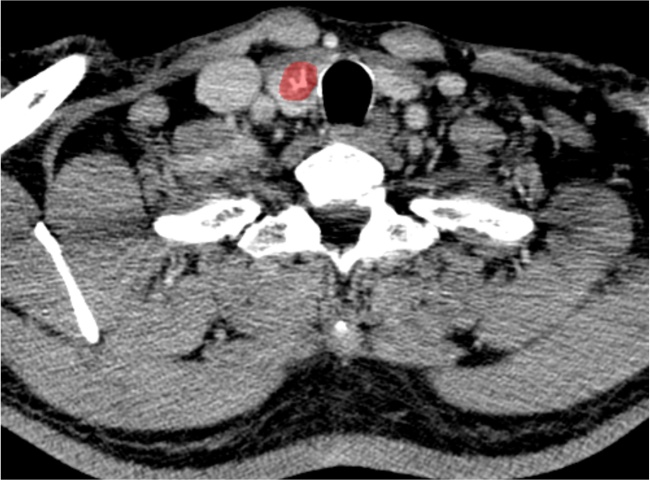

注:甲状腺增强静脉期(a)及相应ROI区域勾画(b)。

Figure 1. CT imaging of a 54-year-old male patient with thyroid

1. 男性54岁甲状腺CA患者CT影像

由2名具有6年以上甲状腺CT诊断经验的放射科主治医师采用联影URP组学软件在CT图像上分别逐层手动勾画ROI (图1图2),然后自动提取影像组学特征,通过组内相关系数(intraclass correlation coefficient, ICC)检验保留ICC ≥ 0.75的特征,依次通过最大相关最小冗杂(max-relevance and min-redundancy, mRMR)及最小绝对收缩与选择算子(least absolute shrinkage and selection operator, LASSO)算法筛选影像组学特征。行LASSO回归分析时,通过10折交叉验证进行特征降维,得到最优超参数λ值,影像组学评分(Radscore)。最终基于随机森林、逻辑回归、支持向量机构建影像组学模型。